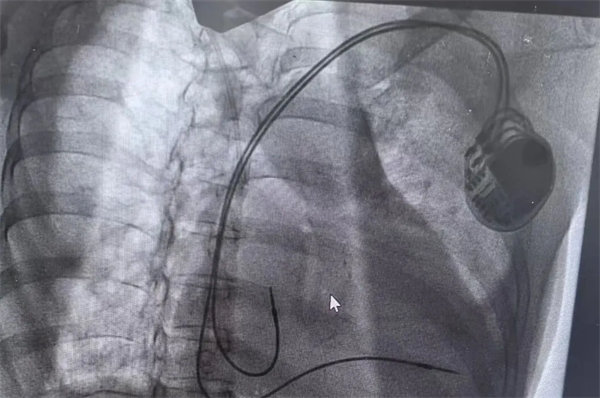

在充分術前準備和家屬的理解支持下,心血管內一科主任翟向偉副主任醫師、陳萬林副主任醫師及介入導管室團隊為患者實施了雙腔心臟永久性起搏器植入術。通過左側腋靜脈入路,精準、輕柔操作順利植入起搏器。術后經過醫護團隊的精細診治,起搏器囊袋如期愈合,患者可自由活動,生活質量得到有效改善?;颊呒凹覍俾冻隽司眠`的笑容。